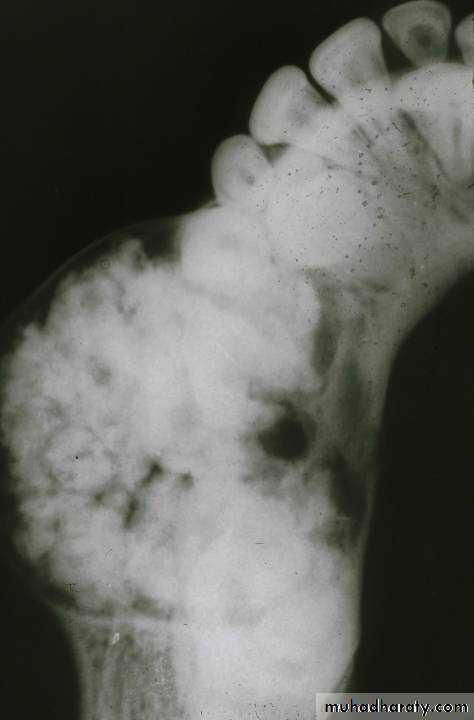

• Early lesions are radiolucent with smooth, well-defined contours.

• Later a well-defined radiopaque appearance develops.• The compound type shows apparent tooth shapes while the complex type appears as a uniform opaque mass with no apparent tooth shapes present.

Odontoma

Radiographical features

• Most odontomas are small and do not exceed the size of a normal tooth in the region.

• However, large ones do occur and these may cause expansion of the jaw.• Most odontomas are asymptomatic and as a result are discovered upon routine radiographic examination.

• Odontomas may block the eruption of a permanent tooth and in these cases are often discovered when “searching for” the “missing” tooth radiographically.